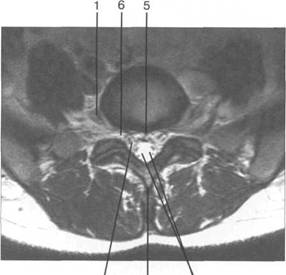

MPT. Cw_v.